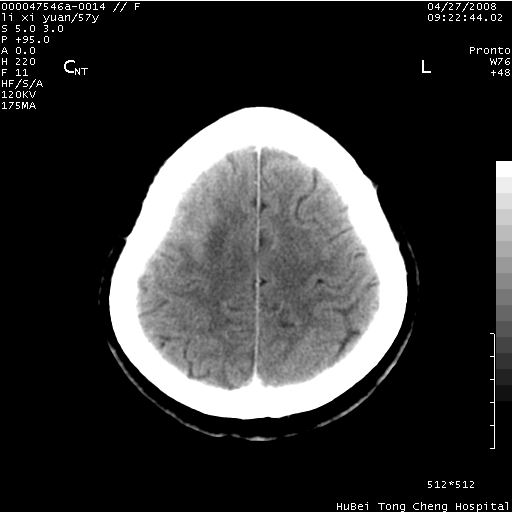

以下是引用余辉在2008-4-27 14:02:00的发言:[br]病灶位于中央沟前方?位于额叶?高密度灶,灶周水肿不明显,病灶似沿脑沟走行,强化明显,局部层面呈现环状强化,考虑1脑表面血管性疾病,如血管瘤,血管扩张,灶内血栓形成,其次考虑肿瘤如脑膜瘤、转移瘤,胶母等

以下是引用形影不离在2008-4-27 14:13:00的发言:[br]考虑胶质瘤可能性大,不排除慢性炎性肉芽肿。建议mri检查。